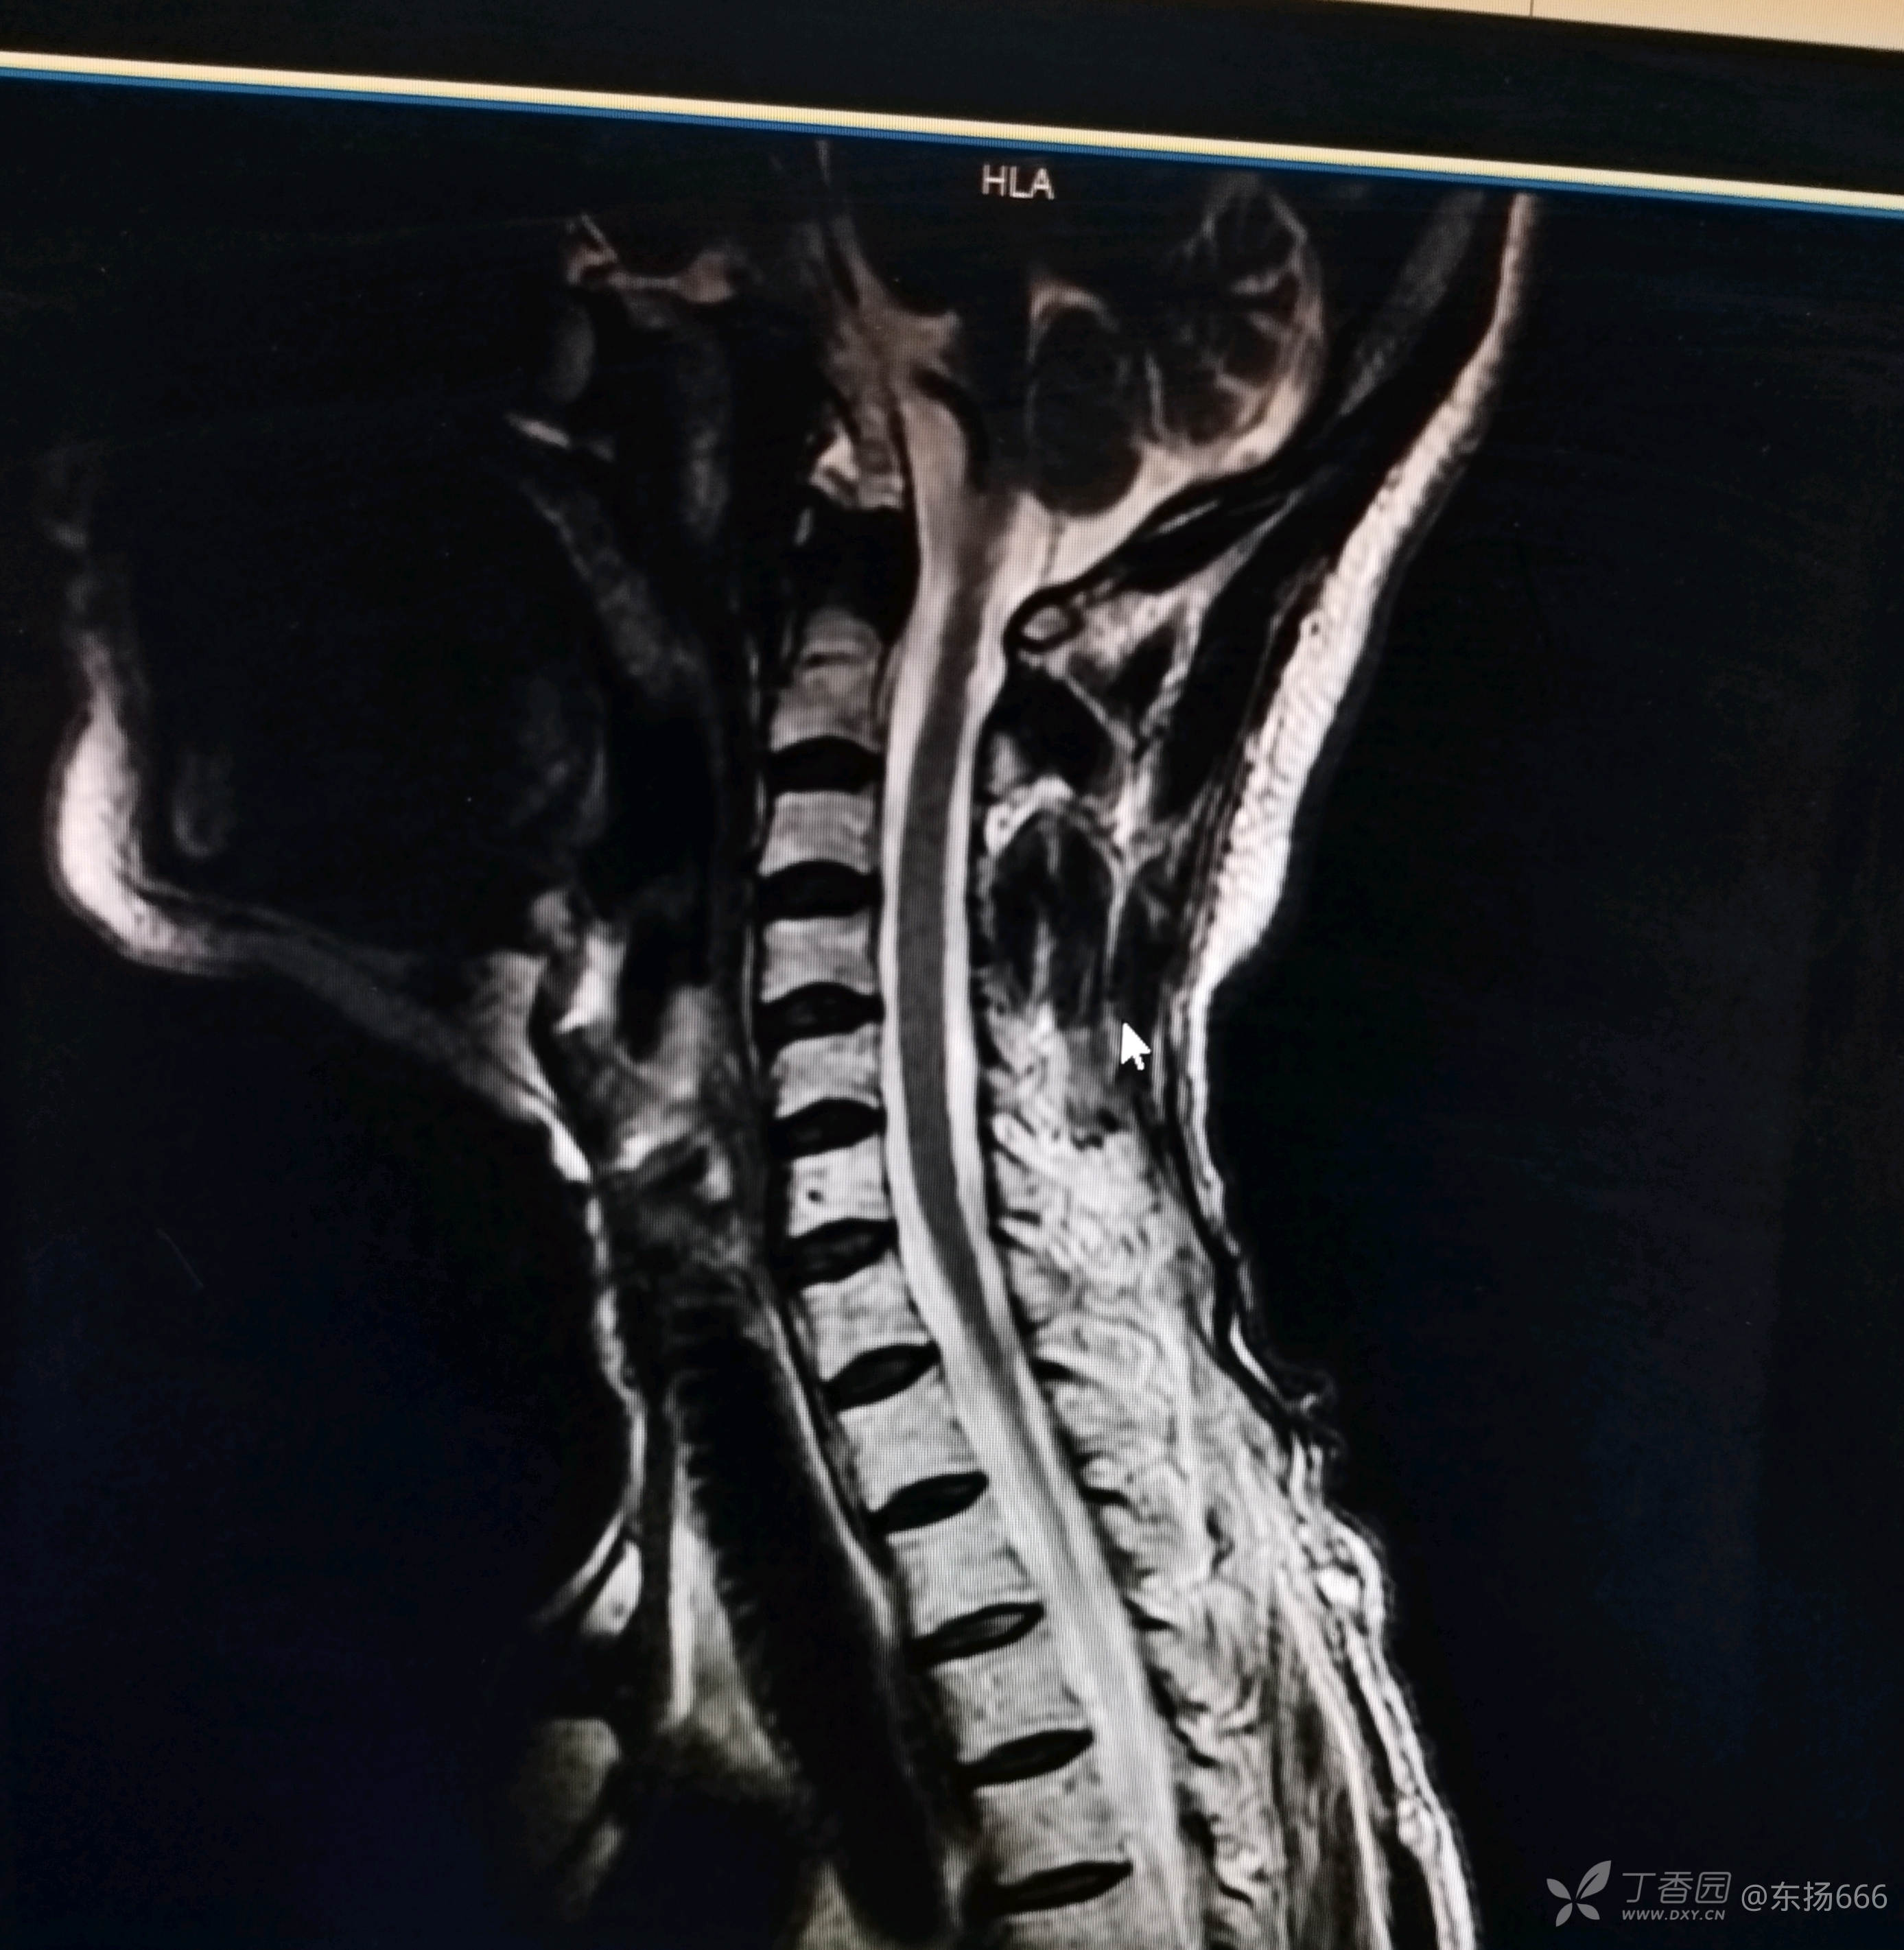

我院行颈椎MR示:颈椎间盘退行性病变。C2-7椎间盘突出